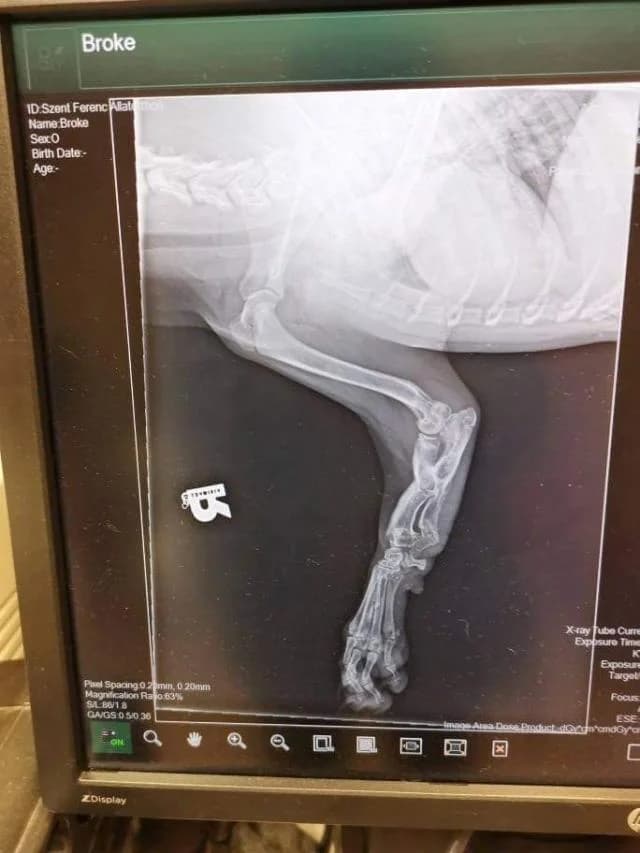

Noémi, ez a bájos, fekete kutyalány még alig múlt fél éves. Egy ilyen kölyök csupa játék, csupa vidámság, szertelenség. Futkosás, rohangálás, bukfencezés, hempergés, gondtalan birkózás a többiekkel, ez tölti ki a napjait. De neki nem ennyire vidám a jelene, a jövője pláne nem. Sajnos olyan állapotban vannak a mellső lábai, hogy az altatás is felmerült javaslatként, mert felnőtt korára komoly fájdalmai lesznek. Persze mi nem adjuk fel, de az, hogy előbb az egyik, majd a másik mellső lábát amputálni kell, az sajnos szinte elkerülhetetlen. Tudjuk, nagy áldozatot vállal, aki így is örökbe fogadja, elfogadja az állapotát, vele lesz, amikor már a műtétek várnak rá és segít neki abban, hogy ebben a nem mindennapi nehézségekkel járó helyzetben Noémi boldog, gazdájáért rajongó kutya legyen. Noémit kizárólag olyan helyre mehet, ahol nincs sok lépcső, és kertes házban is csak bent lakhat. Kérjük, aki egy kicsivel is hozzá tudna járulni betegeink orvosi ellátásához az alábbi számlaszámra utaljon! Erste: 11991102-SWIFT KÓD: GIBAHUHB Nemzetközi számlaszám: HU48 1199 1102 0000 A megjegyzésbe kérjük beleírni: Noémi Figyelem! Noémi az állatotthon csömöri telephelyén él. Látogatása előzetes bejelentkezés után történhet.